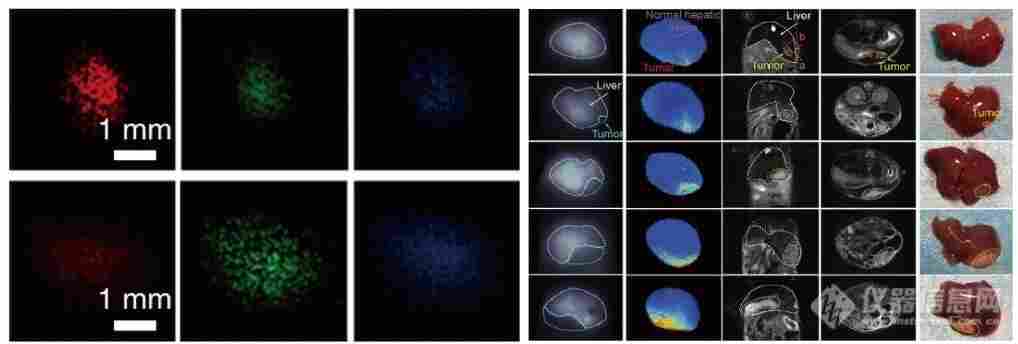

1.腫瘤研究:在腫瘤早期檢測中,該系統(tǒng)可利用高靈敏度和高分辨率,*識別微小腫瘤病灶,實現(xiàn)腫瘤的早發(fā)現(xiàn)、早診斷。在腫瘤手術(shù)中,實時成像能清晰顯示腫瘤邊界及周圍組織情況,輔助醫(yī)生更*地切除腫瘤,降低殘留風(fēng)險。同時,還可用于監(jiān)測腫瘤治療效果,評估藥物對腫瘤細(xì)胞的作用,為個性化治療方案制定提供依據(jù)。

圖2:多指標(biāo)腫瘤標(biāo)志物及腫瘤微環(huán)境定量檢測